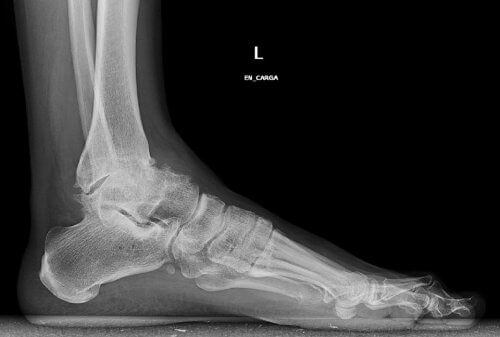

Toenemende slijtage van het kraakbeen in het enkelgewricht is de oorzaak van dit type osteoartritis. Als we ouder worden, is het heel normaal dat de enkels stijf worden en misvormingen zich ontwikkelen.

Klassieke botsporen kunnen ook optreden. Die maken de aandoening nog pijnlijker en beperken je nog meer in je bewegingen.

- Traumatologen vermelden ook deze eigenaardige oorzaak: de misvorming van de enkel zelf. Mensen met platvoeten hebben soms meer kans om na verloop van tijd osteoartritis te ontwikkelen.